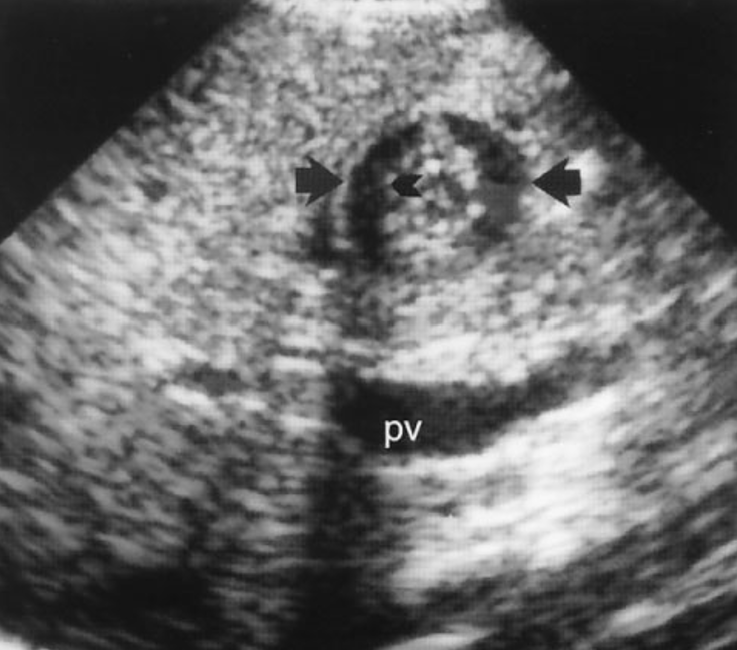

what is a wheel within a wheel lesion?

associated with hepatic candidiasis

appears with a peripheral hypoechoic zone, an inner echogenic wheel, and a hypoechoic center

what is a bull’s eyes lesion?

AKA target sign

occurs when center of lesion contains inflammatory cells become calcified

causes it to appear echogenic in the center which a hypoechoic rim surrounding the center.